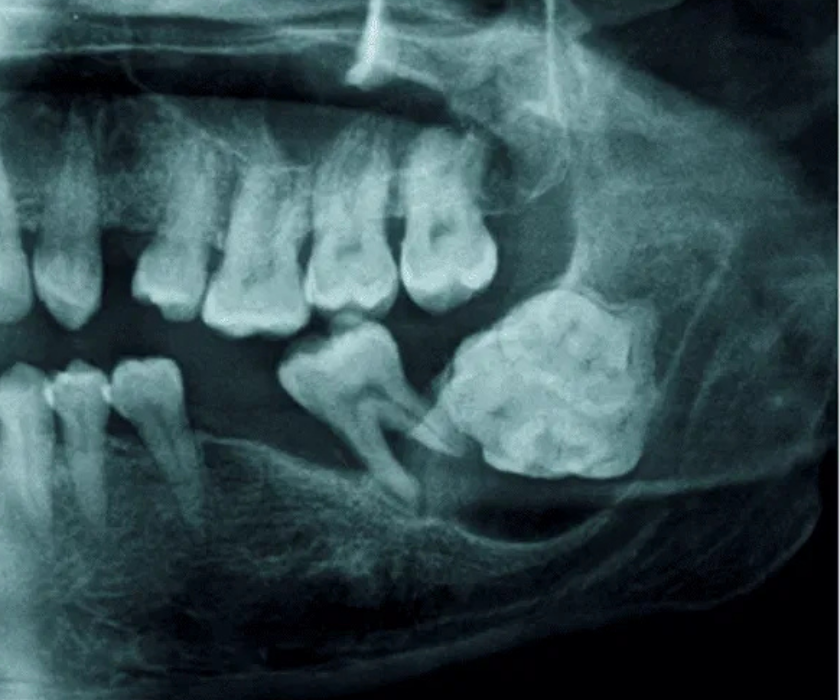

Bước 1: Thăm khám và chụp X-quang

Bác sĩ tiến hành kiểm tra tổng quát tình trạng răng miệng, xác định răng khôn mọc lệch, mức độ cản trở của răng với các răng lân cận. Đồng thời, khách hàng được chụp X-quang Panorex hoặc Cone Beam 3D để đánh giá vị trí, hướng mọc và tình trạng xương hàm. Dựa vào hình ảnh này, bác sĩ sẽ lập kế hoạch nhổ răng an toàn, hạn chế tối đa rủi ro.

3. Gây u, nang xương hàm

Quá trình mọc răng khôn kéo dài hàng năm và thường xảy ra một phần nhỏ mỗi lần. Nếu không xử lý, răng dễ nhiễm trùng mãn tính, hình thành u nang ở phần xương hàm hoặc nang thân răng, gây tổn thương nghiêm trọng đến hàm và các răng kế cận.

U nang xương là biến chứng của răng khôn